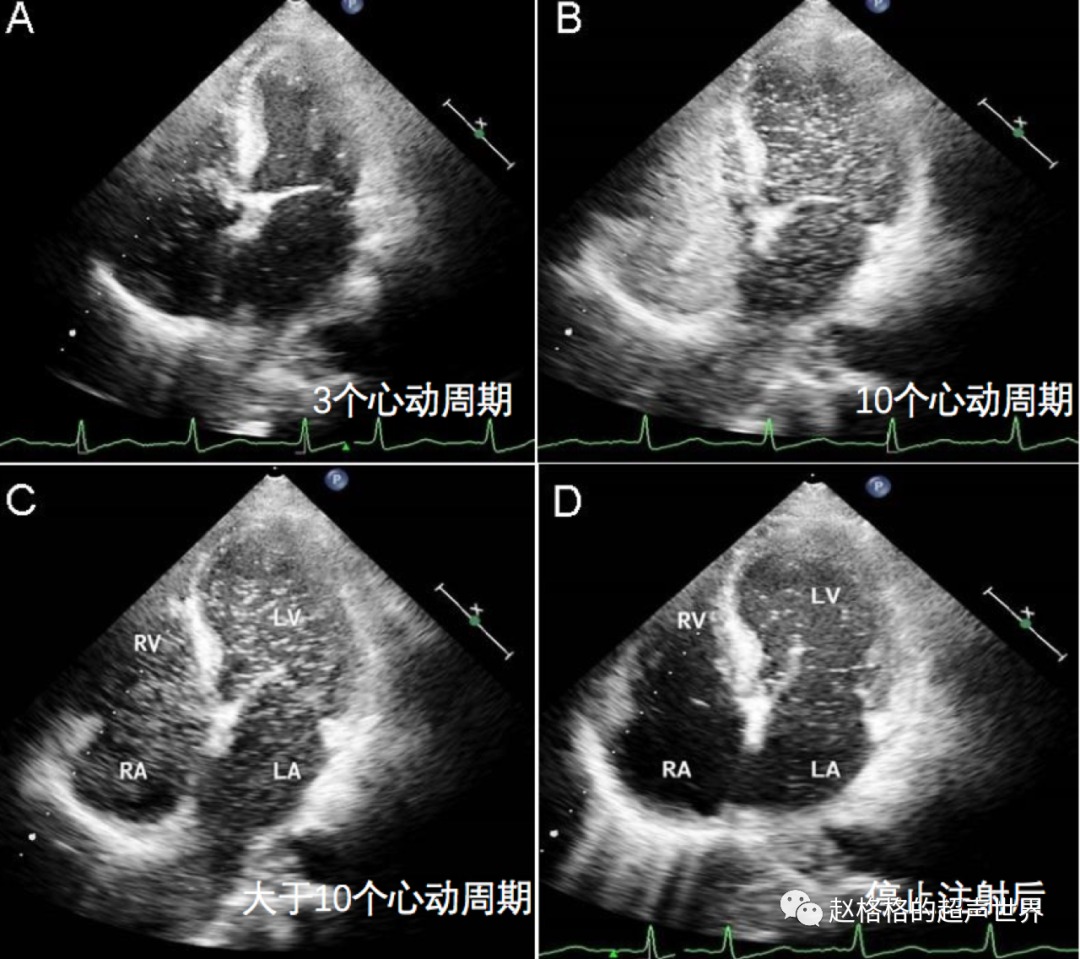

格格答:一般认为,左心显影迟于右心显影≤3个心动周期,多考虑为房水平分流,>6个心动周期多考虑存在肺动静脉水平分流,而在4~6个心动周期时二者均有可能。

这是一位60岁的肝硬化男子,胸痛,呼吸急促就诊,氧饱和度低,胸部X线和肺功能检查正常。

图A:在右心房和心室出现后,左心房中出现大量微气泡的延迟出现大于三个心动周期,这提示了肺动静脉瘘。

图B、图C:即使经过10个心动周期,左心室和右心室的微气泡密度也相同。

图D:停止注射后,左心室中出现微气泡,而右心室中没有气泡。